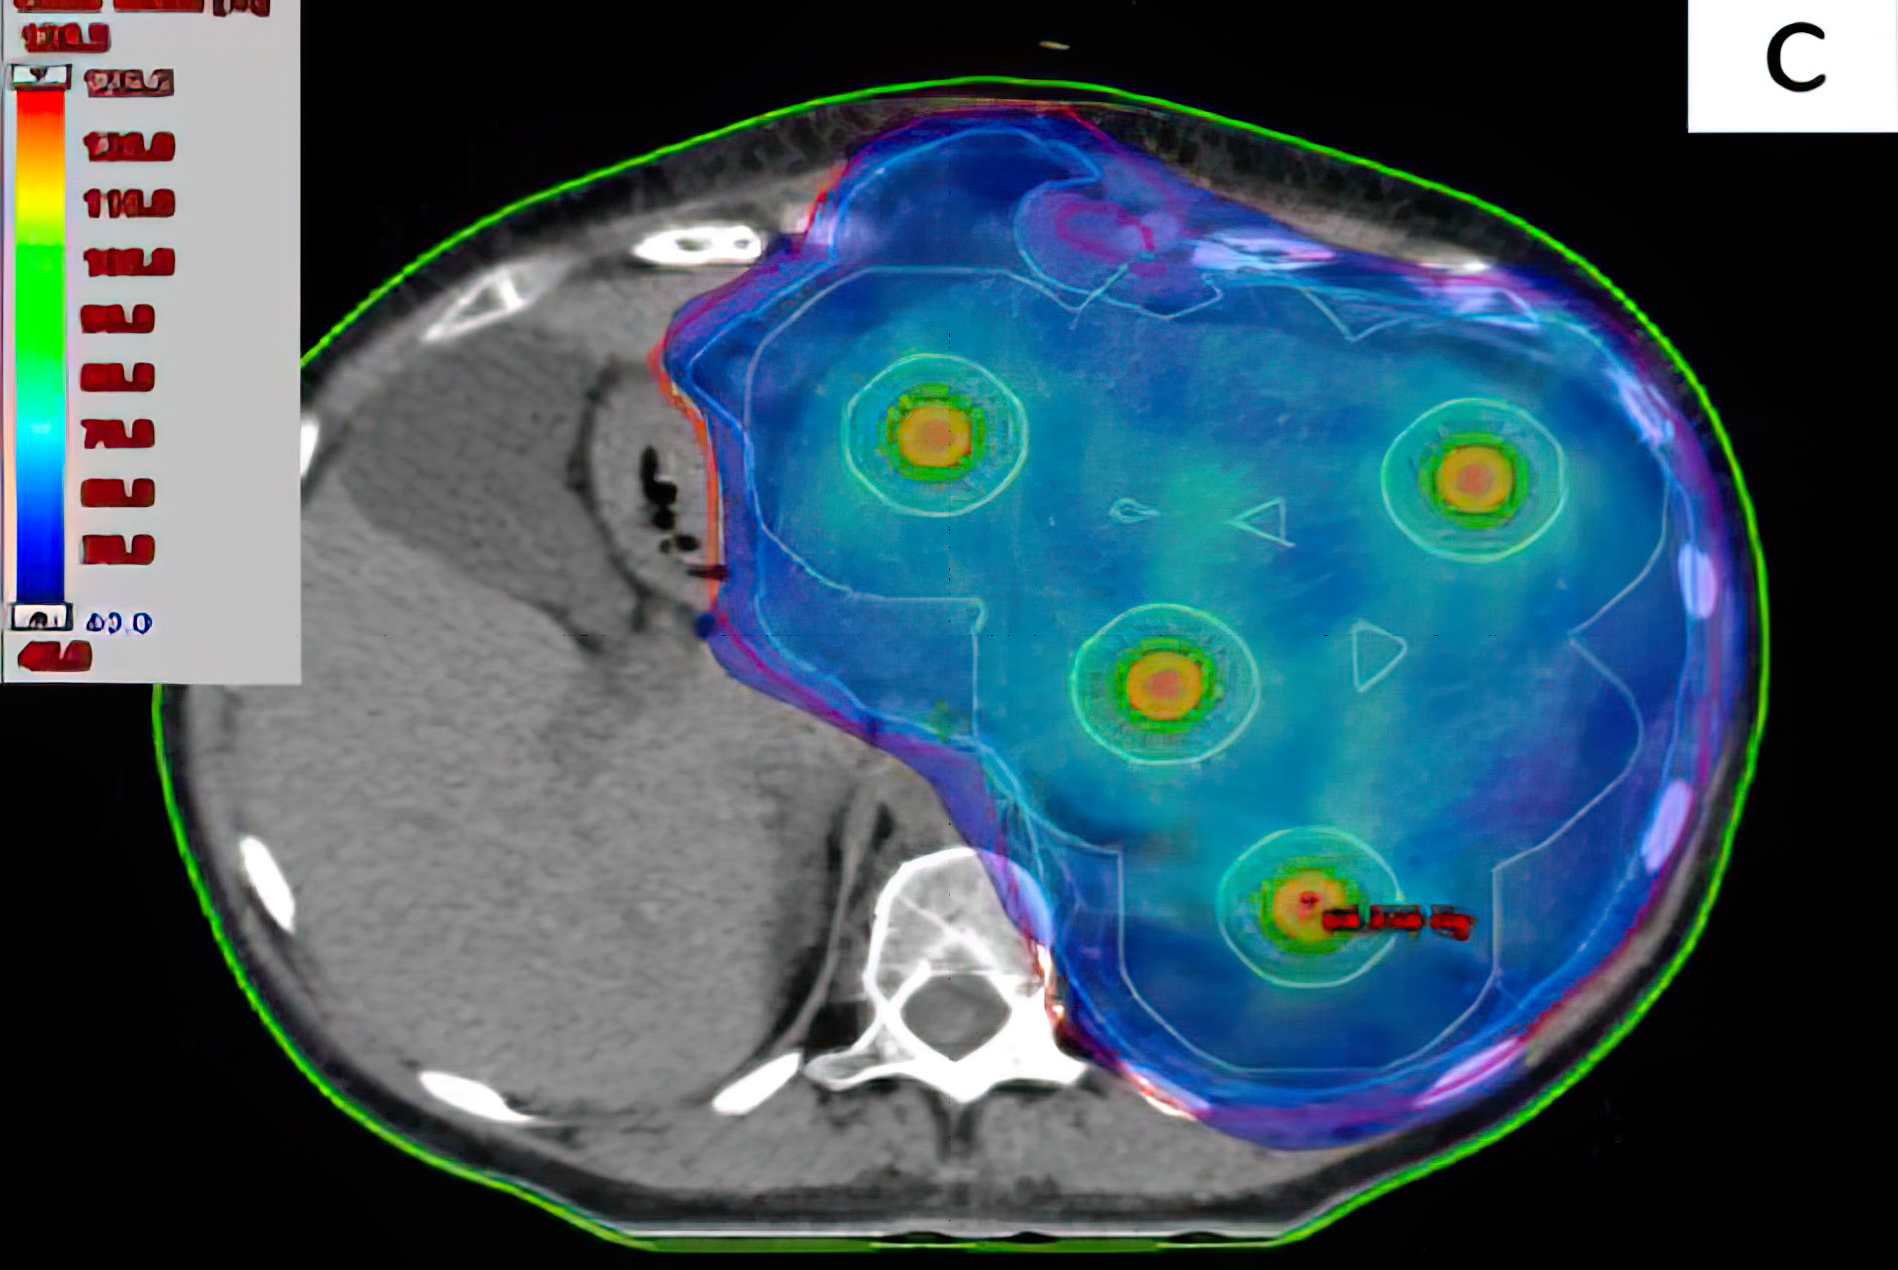

CRnR’s unique beam structure produces a Photon Spread Out Peak (PSOP) effect which closely replicates the effects of the Proton SOBP with a region of maximum dose at the target and a reduced dose before and after the target.

Safer treatment: Superior (reduced) dose to neighbouring tissue thanks to the Bragg Peak Like profile of the focused x-ray photon beam. See Isodose comparison in sample lung case below, showing reduced radiation to the heart, lung and liver vs Linac.